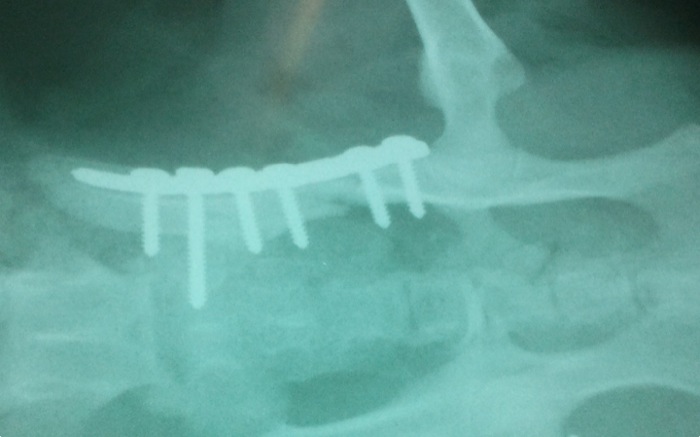

El ileon del mismo lado queda bien posicionado y aunque se valora una fijación adicional mediante 2 tornillos se descarta ante la aparente estabilidad. No se quiere prolongar el tiempo quirúrgico ante el estado aún delicado del paciente, también por ello se pospone la siguiente cirugía.

Dos días mas tarde se interviene la cadera contralateral dado que el paciente había evolucionado comiendo a las 12h y se empezaba a levantar y dar algún paso en la jaula de hospitalización.

La unión es satisfactoria y se normaliza e tamaño del canal pélvico.